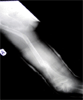

Progress

Union with stable hip and length restoration